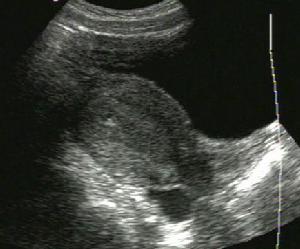

葡萄胎陰道出血是葡萄胎最早出現的症狀般在停經周左右開始有陰道出血呈暗紅色量多少不定時斷時續或綿延不斷但隨時可有大量出血如在排出的血中見到水泡狀物即可確診患者有貧血貌檢查時子宮異常增大超出妊娠月份的大小側或雙側卵巢因囊性變而增大由於增生的滋養細胞產生大量HCG故血尿HCG增高明顯超過正常妊娠的水平B超檢查顯示子宮增大子宮內回聲豐富宮腔內充滿閃亮密集光點如雪花紛飛狀沒有胎兒及其附屬物的影像。